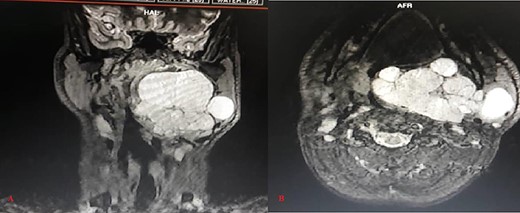

Magnetic resonance imaging showed large lobulated well-defined homogenously hypointense lesion on T1 WI and hyper intense lesion on T2 and STIR WI in the left para-pharyngeal space extending from the skull base to the hyoid bone. Medially, it was bulging in the nasopharynx and the oropharynx, significantly compromising the airways (Fig. 1).

Magnetic resonance STIR WI imaging (A: Coronal, B: Axial) shows large, lobulated, well defined and hyper intense soft tissue lesion in the left para-pharyngeal space with the lesion extending from the skull base to the hyoid bone, significantly compromising the airways

The deep lobe of the left side parotid gland was not separately identified from the lesion, and it was abutting the neurovascular bundle of the parotid gland from the inner aspect.